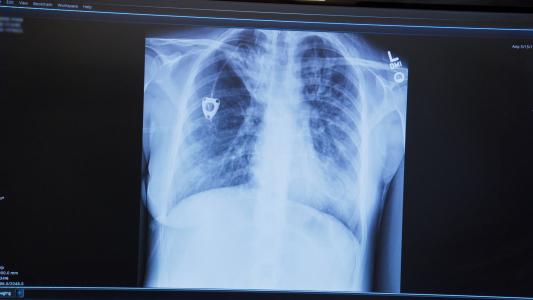

Scientists grew a mini brain in a lab. It has human-like brain waves.

For the first time, a lab-grown mini brain has brain waves. Researchers can now launch new ways to study brain disorders. But the question of consciousness in the brain-like organoid could raise concern.